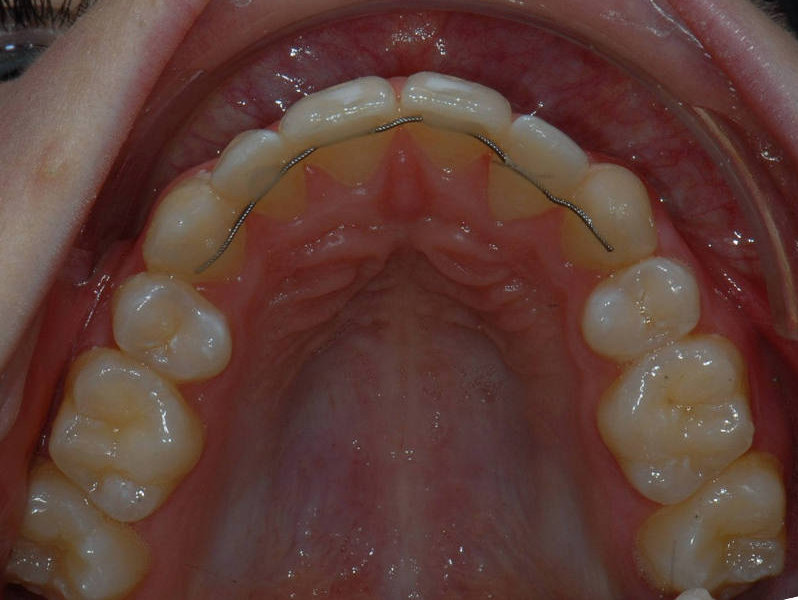

TwistFlex retainer

Flatwire retainer